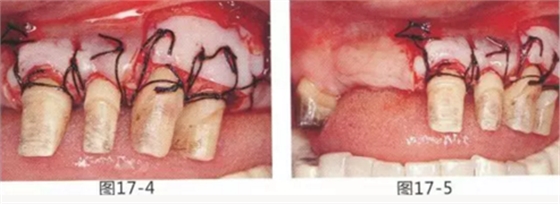

圖17-4 左上1,2進行齦瓣根尖側(cè)轉(zhuǎn)移,左上3,4進行游離牙齦移植,在去除牙周袋的同時獲取附著齦。

圖17-5 牙周治療完成后的正面照。左上3,4部位處游離齦移植片的上端通過骨膜縫合固定在頰側(cè)嵴頂部。這樣可以使其愈合效果與齦瓣根尖側(cè)轉(zhuǎn)移相同。